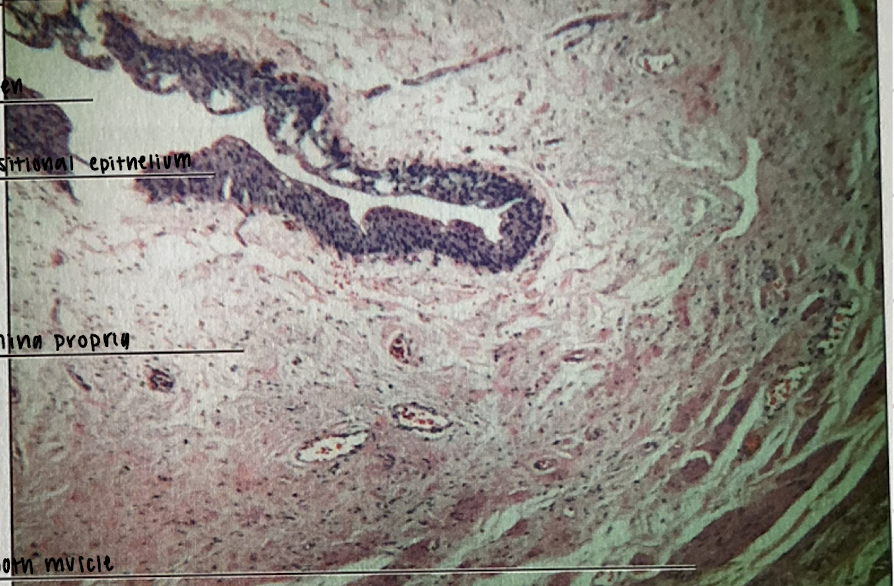

ureter

ureter

tubular conduit of urine flow